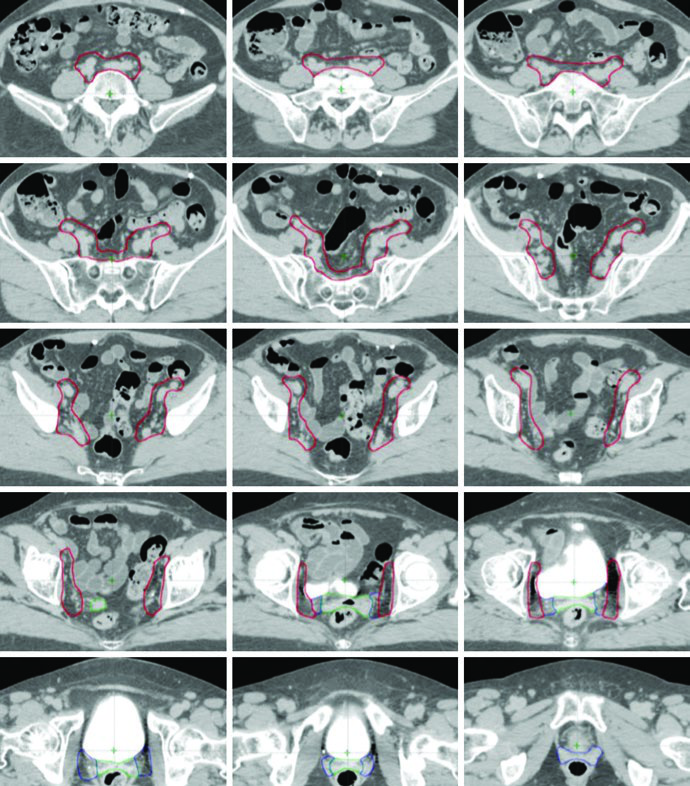

O delineamento pós-operatório de câncer cervical e endometrial utiliza múltiplos CTVs — CTV1, CTV2 e CTV3 — para permitir expansões anisotrópicas de CTV para PTV. Cada componente tem função anatômica e margem distintas, conforme definido no ensaio clínico randomizado TIME-C.

Definição dos Volumes-Alvo: CTV1, CTV2 e CTV3

| Volume | Definição | Expansão para PTV |

|---|---|---|

| CTV1 | Cúpula vaginal, incluindo tecido adiposo e partes moles anterior e posterior à cúpula entre a bexiga e o reto | 15 mm |

| CTV2 | Tecidos paravaginais/parametriais, vagina proximal (excluindo a cúpula) | 10 mm |

| CTV3 | Regiões nodais ilíaca comum, ilíaca externa e ilíaca interna — vasos pélvicos + expansão de 7 mm (excluindo osso, músculo e intestino), tecidos entre vasos ilíacos internos e externos, linfonodos pré-sacrais (tecidos moles anteriores ao S1-S2, mínimo 1,0 cm). Limite superior: 7 mm inferior ao interespaço L4-L5. Limite inferior: aspecto superior da cabeça femoral | 7 mm |

Fonte: Target Volume Delineation and Field Setup, 2nd Edition (Table 20.1)

Em relação ao CTV1, a porção anterior do ligamento uterossacral é removida durante a histerectomia radical. Por isso, a fáscia mesorretal serve como estrutura substituta para a borda posterior da cúpula vaginal e do paramétrio no CTV. Boost vaginal pode ser considerado em pacientes de maior risco de recorrência por fatores como invasão estromal cervical, histerectomia supracervical, LVSI extenso ou envolvimento vaginal extenso.

No câncer de endométrio, o CTV3 é modificado para incluir a região pré-sacral quando há invasão estromal cervical. Nos casos com envolvimento patológico de linfonodos para-aórticos ou ilíacos comuns altos, utilizam-se campos estendidos pélvico-para-aórticos, com o limite superior do CTV estendendo-se ao interespaço T12-L1 ou L1-L2, ou à vasculatura renal.

Quando há envolvimento do terço distal da vagina, os linfonodos inguinais devem ser contornados continuamente desde os linfonodos ilíacos externos até 2 cm caudal à junção safeno-femoral.

Composição do PTV Final

Os PTVs são criados para cada CTV com margens diferentes — 15 mm para CTV1, 10 mm para CTV2 e 7 mm para CTV3 — refletindo o grau de movimento interno e incerteza de setup de cada componente. O PTV final usado para planejamento é gerado pela união de PTV1, PTV2 e PTV3: PTV = PTV1 ∪ PTV2 ∪ PTV3.

Quando se utiliza a abordagem de ITV, o CTV1 e CTV2 devem ser contornados nas TC com bexiga cheia e vazia e fusionados para gerar o ITV. Uma expansão de 7 mm no ITV gera o PTV, que é combinado com o PTV3 para o PTV final. Essa estratégia é particularmente relevante porque a cúpula vaginal e os tecidos paravaginais sofrem deslocamento significativo com as variações de enchimento vesical.